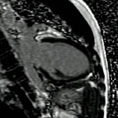

Cardiac MRI

Evaluating Heart Function. MRI function is the gold standard in evaluation of heart function which is of vital importance in cardiac problems. These pictures are obtained without IV contrast.

Abnormal Heart Function. This video shows that the tip of the heart no longer contracts normally as a consequence of a heart attack.

Healthy Heart